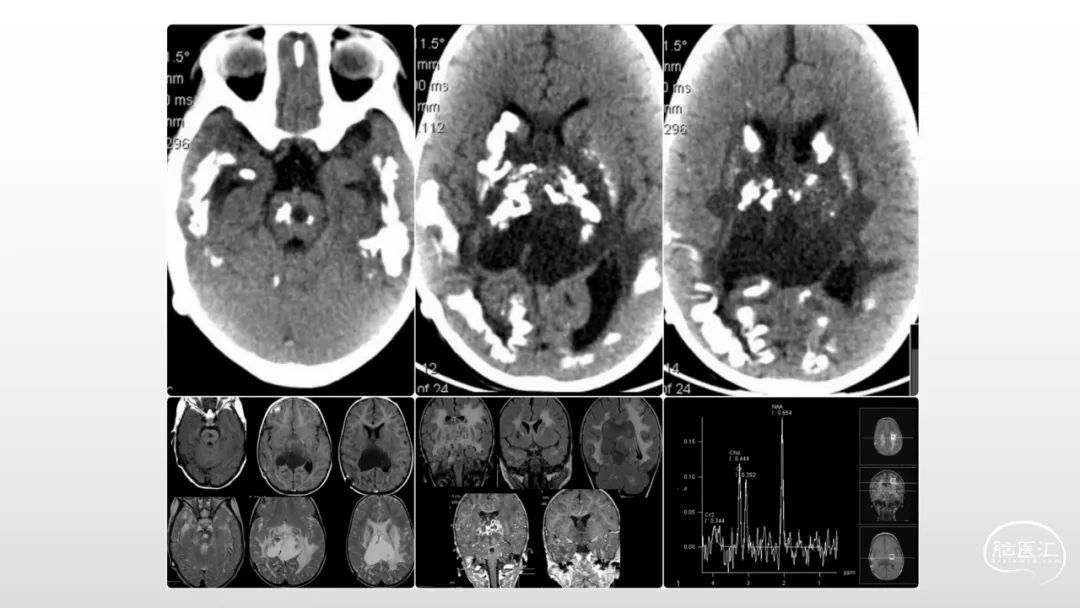

颅脑影像诊断基础知识讲座:感染和免疫性疾病1